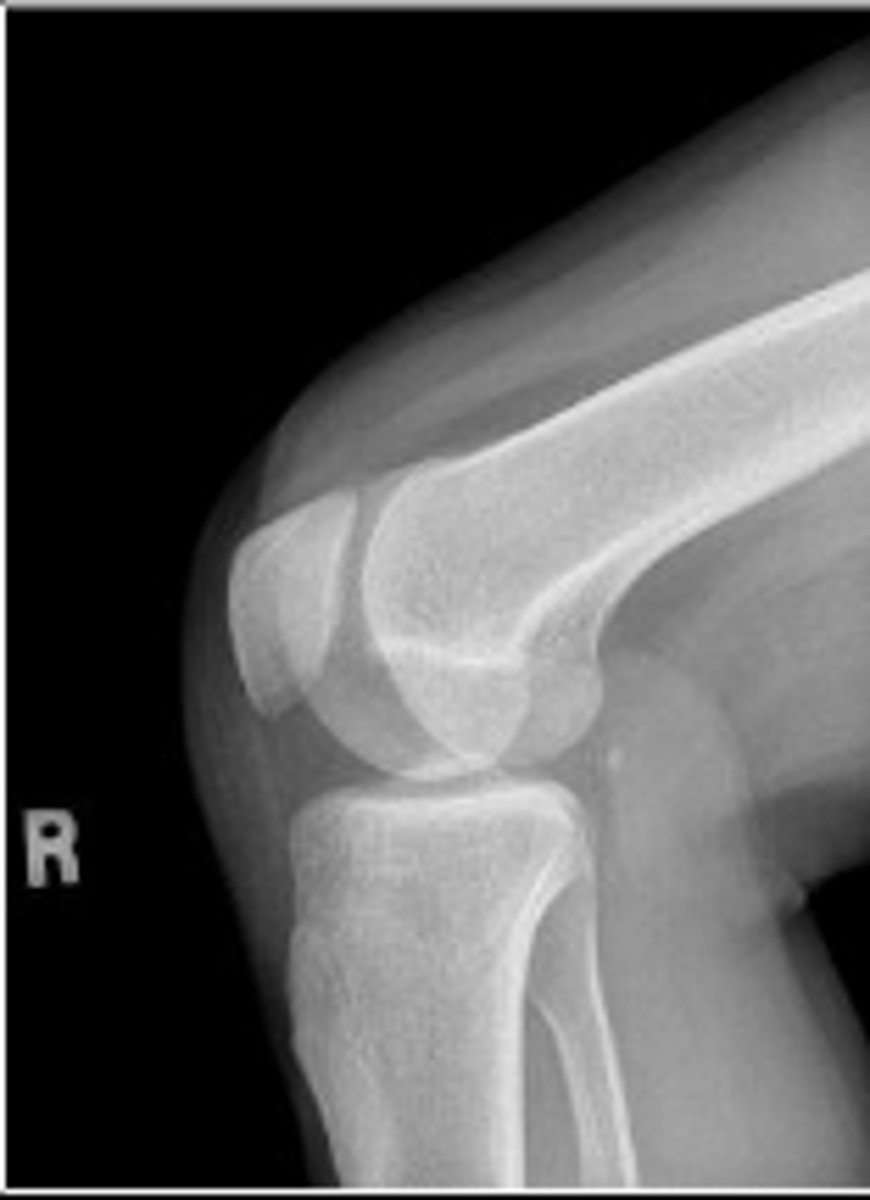

Right lateral knee

What is the name of the radiographic view?